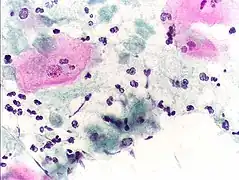

Micrograph of a normal pap smear

Micrograph of a Pap test showing a low-grade intraepithelial lesion (LSIL) and benign endocervical mucosa. Pap stain.

Micrograph of a Pap test showing trichomoniasis. Trichomonas organism seen in the upper right. Pap stain.

Endocervical adenocarcinoma on a pap test.

Candida organisms on a pap test.

Viral cytopathic effect consistent with herpes simplex virus on a pap test.

Normal squamous epithelial cells in premenopausal women

Atrophic squamous cells in postmenopausal women

Normal endocervical cells should be present into the slide, as a proof of a good quality sampling

The cytoplasms of squamous epithelial cells melted out; many Döderlein bacilli can be seen.

Infestation by Trichomonas vaginalis

An obviously atypical cell can be seen